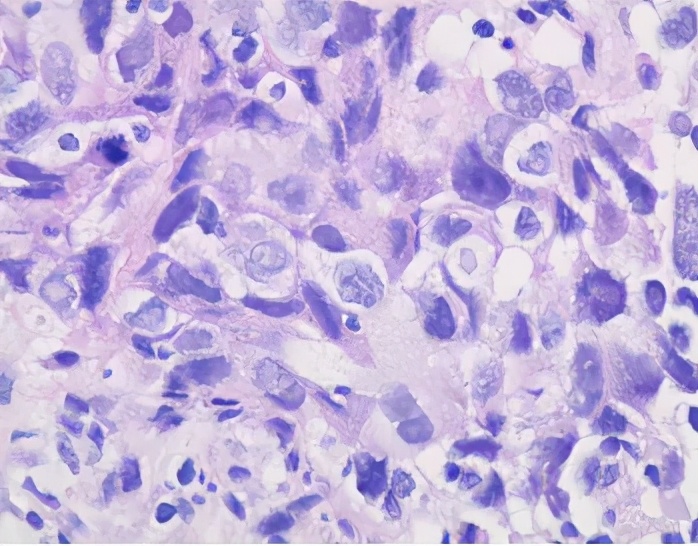

2019-10-31 CT引导下穿刺活检

病理示:右上肺浸润性癌,结合免疫组化结果,符合肺腺癌(实性生长方式)。免疫组化:CK7(+),TTF-1(+),CK5/6(-),P40(-),ALK(D5F3)(-),ALK(D5F3)Neg(-)。

基因测序:EGFR(-),ALK(-),ROS1(-)。